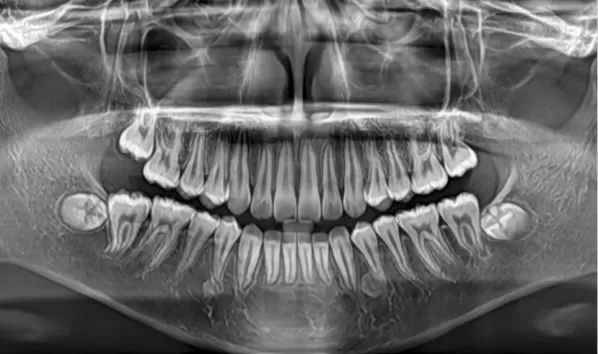

X-rays before treatment

[Panoramic Radiography/Lateral Cephalogram]